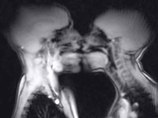

画像は「PLOS ONE」より